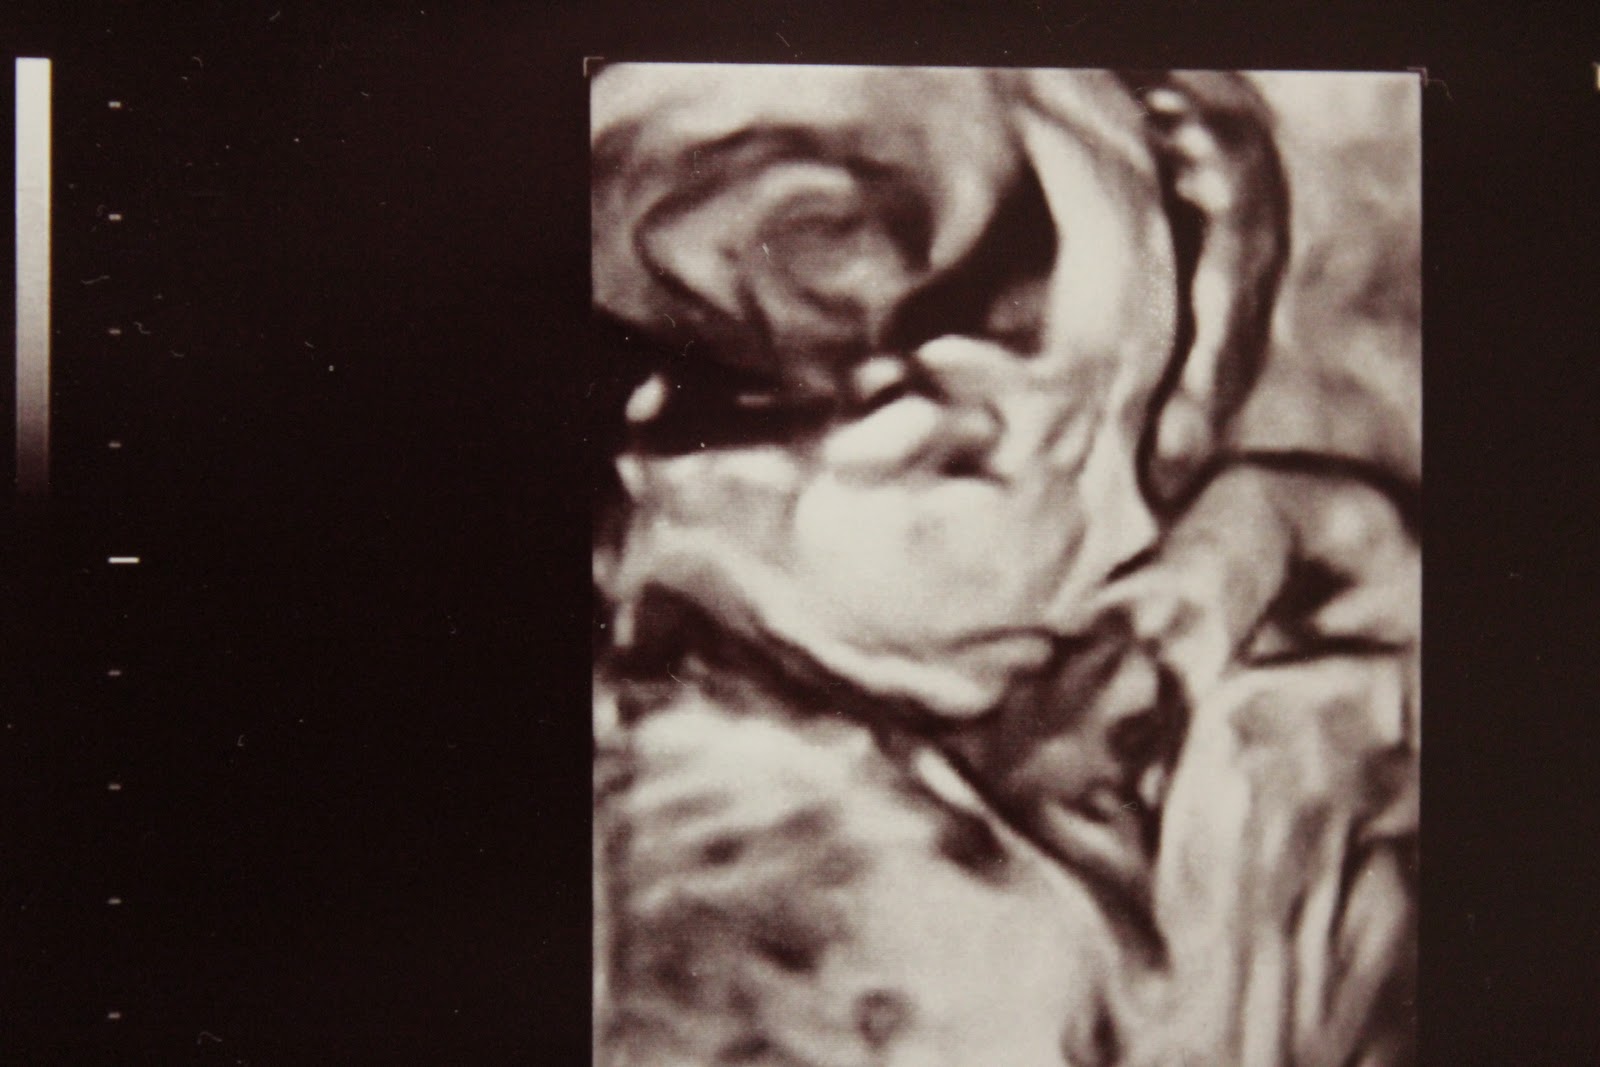

Rakas peukaloinen <3

Marraskuun alussa oli ultra. Sairaalan laitteet oli uusittu ja saatiin nähdä ihanaakin ihanempaa 4D-kuvaa rakkaasta peukaloisesta. Olin ja olen superonnellinen.. pian kahden lapsen äiti. Laskettuaika on maaliskuun puolella eli vielä on kuitenkin aikaa.